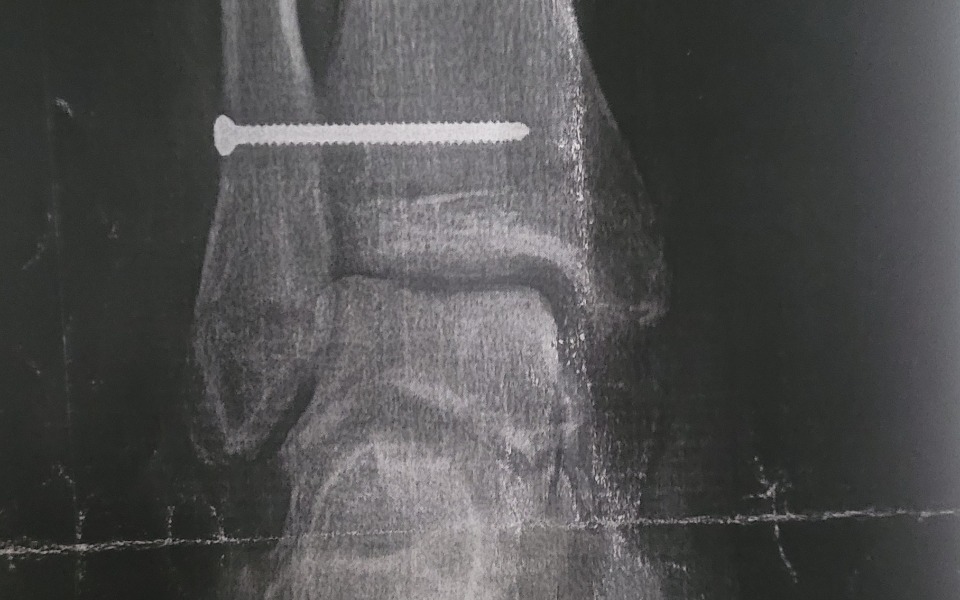

Hej nazywam sie Michał. Zdecydowałem się na zbiórkę pieniędzy, z powodu przechodzenia przez okres po operacji stawu skokowego. Moim celem jest zebranie środków na rehabilitację, która umożliwi mi powrót do pełnego zdrowia oraz pomoże w szybkim powrocie do pracy. Zbiórka pomoże mi pokryć koszty utrzymania mnie oraz mojego małego synka ponadto pokryje koszty czynszu mieszkalnego. Jestem wdzięczny za wszelkie wsparcie, które mogę otrzymać w tej trudnej sytuacji.